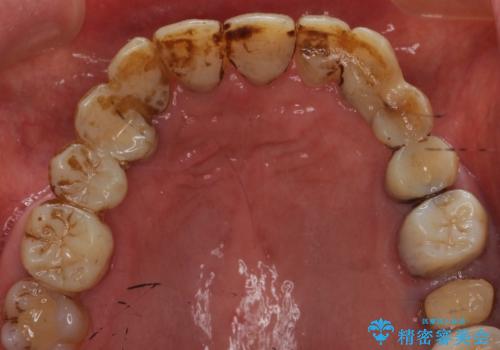

- 日頃からコーヒーをよく飲むそうでべったりとステインが付着していました。

ステインがたくさん付着していたので、エアフローを用いてステインを除去しました。そのため、直後の写真は歯肉からの出血が見られます。